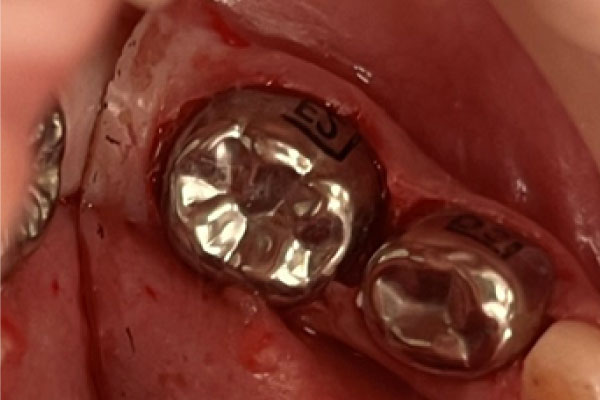

Лечение пульпита: фото До и После

- Зуб рассверливается до пульпы, пораженные ткани (иногда вся пульпа целиком) удаляются, а каналы обеззараживаются.

- Каналы пломбируются. При необходимости восстанавливается коронка зуба или в каналы устанавливается штифт, в дальнейшем будущий основой для зубного импланта.